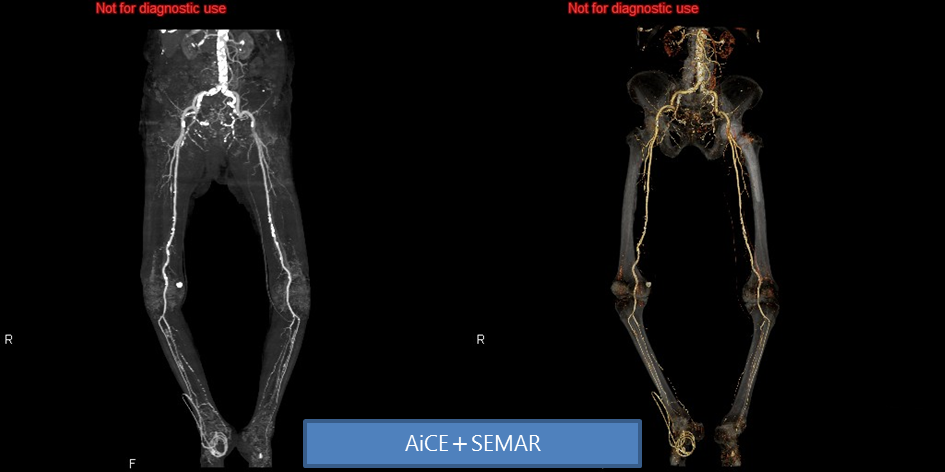

<下肢血管造影CT>

さらにワークステーションを用いる事で、邪魔な骨や臓器を取り除き、任意の方向からの観察が可能となり、レントゲン写真では解りにくい骨折や腹部血管の走行が手術前に確認出来ることで、より正確な診断とより安全な手術が行えます。